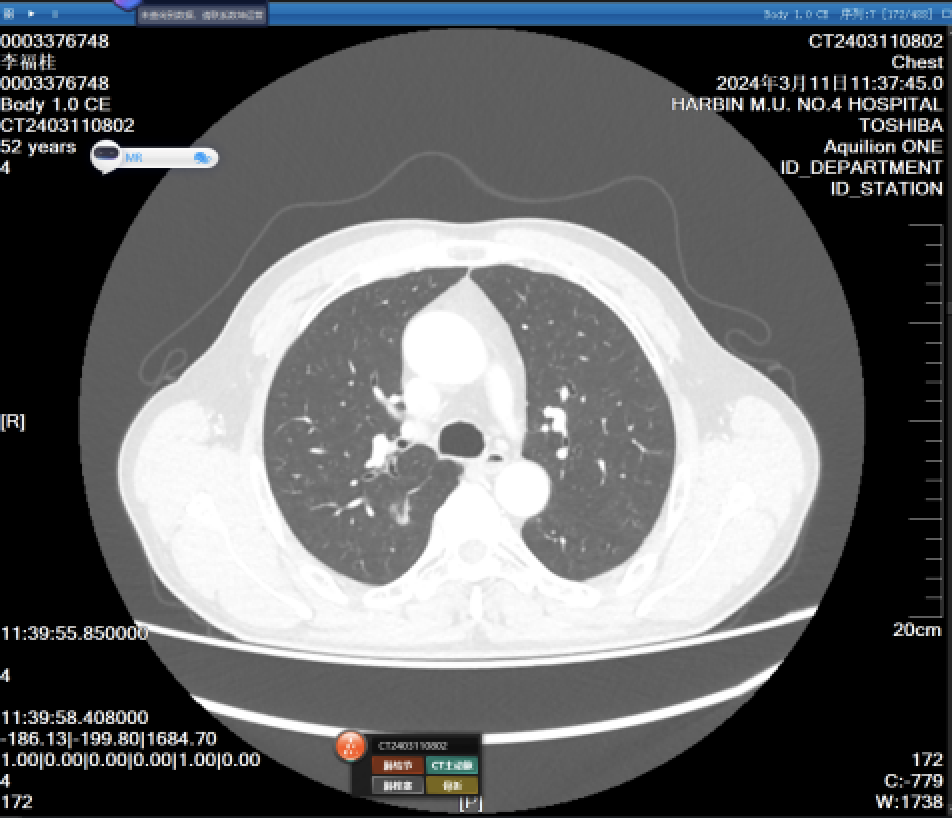

费莱舍尔学会亚实性肺结节CT处理指南

image.png